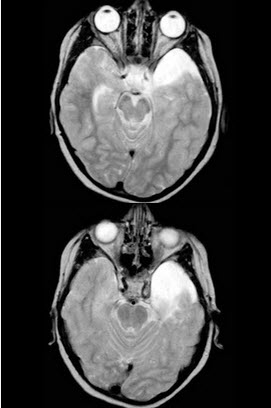

男,7岁,头痛,MRI表现如图,最可能的诊断是()

[单选题]男,7岁,头痛,MRI表现如图,最可能的诊断是()A . 硬膜下血肿B . 硬膜下积液C . Dandy-Walker综合征D . 脑积水E . 颅中窝蛛网膜囊肿